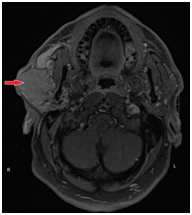

Magnetic resonance imaging (MRI) of the neck revealed a large lobulated mass replacing the superficial lobe of right parotid gland and invades the main parotid duct, without cervical lymph node enlargement Figure2. Features on neck MRI were suggestive of malignant primary salivary gland tumor (likely adenocarcinoma).

Figure 2: Axial Neck MRI Post-contrast fat-saturated T1-weighted images (T1WI) showing a large lobulated mass replacing the superficial lobe of right parotid gland with invasion of the mass into the main parotid duct

Figure 2 Axial Neck MRI Post-contrast fat-saturated T1-weighted images (T1WI) showing A large lobulated mass replacing the superficial lobe of right parotid gland with invasion of the mass into the main parotid duct.